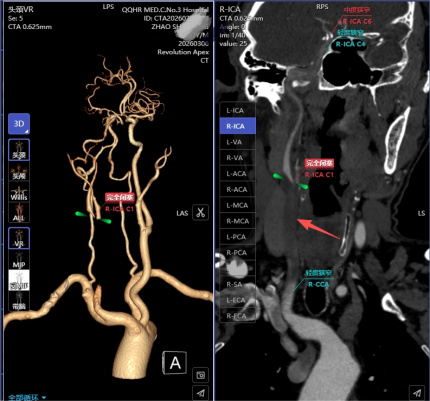

能否快速准确完成影像评估,是决定患者预后的关键。赵先生被迅速送入放射影像诊断中心,一场由Revolution Apex超高端CT主导的“精准侦察”随即展开。这台被誉为“火眼金睛”的设备在极短时间内完成高质效扫描:

头颈部CTA检查:图像清晰地显示,赵先生的右侧大脑中动脉闭塞——这是导致病情的直接原因。